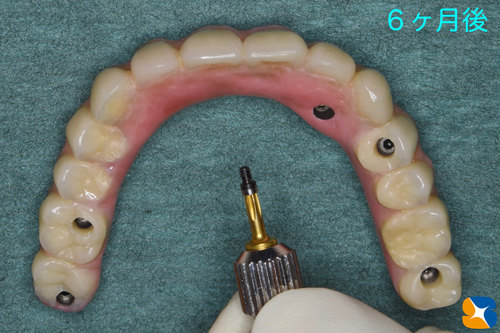

その後、5本のインプラントは確実に定着してくれていましたので、型取りを行いました。

寸分の狂いや隙間が生じないように、丁寧かつ慎重に様々な工程を繰り返しながらネジで完全固定タイプの入れ歯を作成していきます。

完成したネジで完全固定タイプの入れ歯

ネジで完全固定タイプの入れ歯をいよいよ装着していきます。

この夏から使用を始めました。